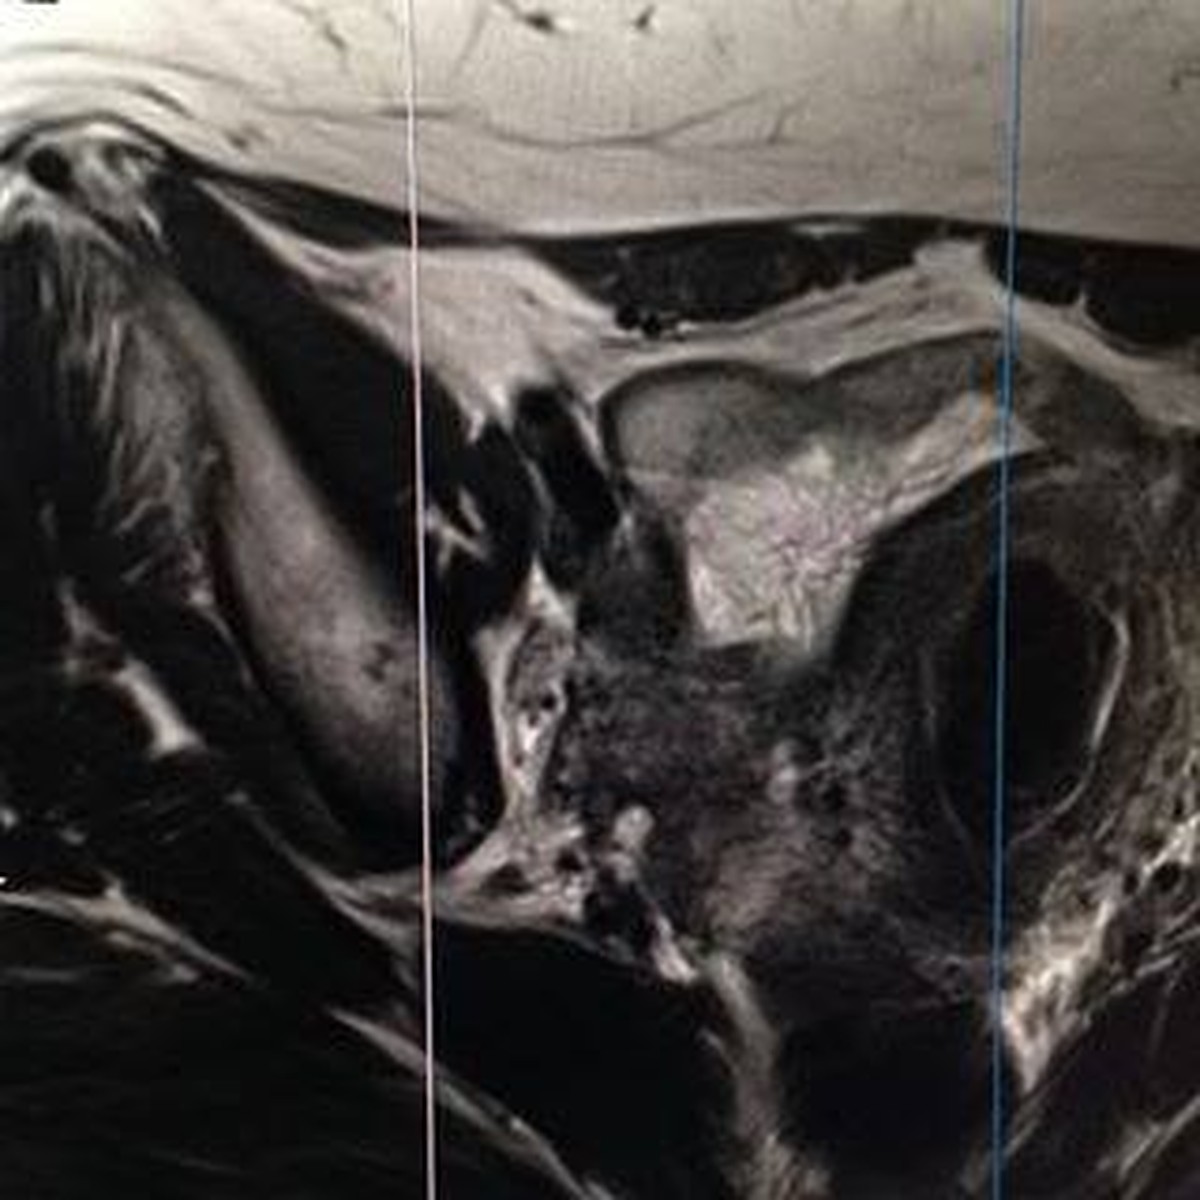

A travers ce film, j’ai voulu trouver, interroger ce dédoublement, en détournant les images médicales de leur usage initial. Grâce à la kinésiologie, j’expérimente un rapport différent au corps, mettant sa propre vie en évidence.

L’expérience de cette réalisation montre de façon saisissante l’intériorité du corps comme un environnement proche de la mer. L’eau offre une vaste gamme d’expressions.

Mon travail consiste à explorer la notion de dédoublement, les relations entre corps et esprit, en évoquant la sensation et la mémoire du corps. À travers le grossissement visuel de détails du corps, la texture, le contraste des images corporelles, l'association et la fusion d'images et le langage d'expression corporelle, cette recherche fait apparaître des problèmes d'intérêt immédiat.